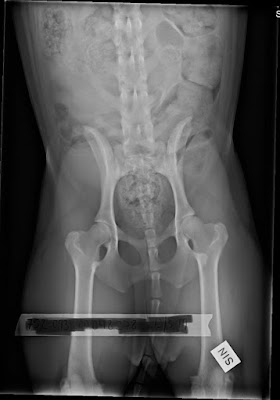

Dagens röntgenbilder

Det är alltid så fruktansvärt nervöst att röntga hundar. SKK har också en förmåga att se något annat än det jag och Åsa (som röntgar) ser. Vi kunde se att det inte är några katastrofer. Inga pålagringar, inga direkta defekter. Troligen ingen som kommer att få problem. Det är det viktigaste. Sen önskar jag mig givetvis enbart HD-fria avkommor. Uppdatering; ALLA VAR FRIA!!!

Freyja A

Messi B

Sansa A

Selma A

Moltas B